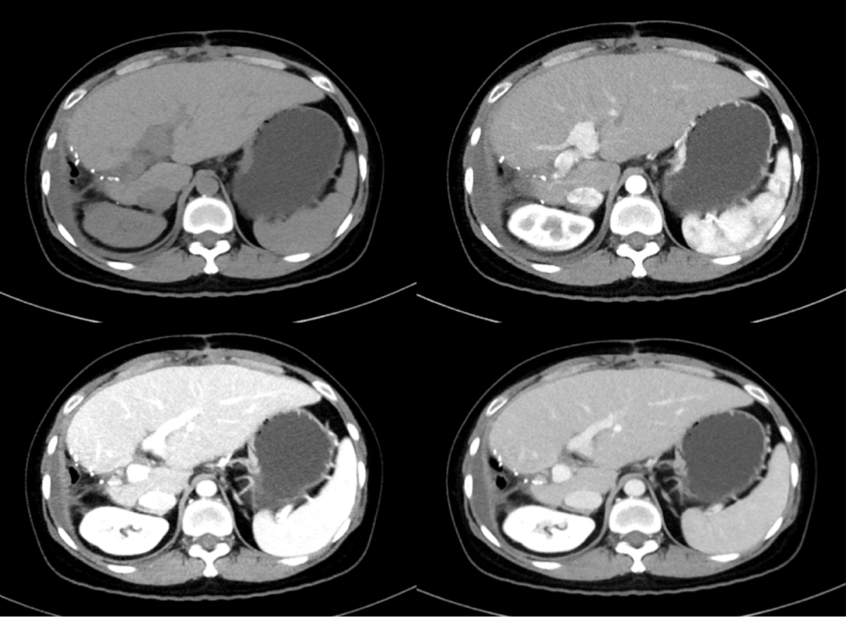

复查:服药后1月,2018-04-18,CT提示双肺转移癌PR。

服药后3月,2018-06-18,CT提示双肺转移癌PR,肝癌未见复发病灶,AFP 73.7ng/mL。

服药后6月,2018-09-06,CT提示双肺病灶PD。

影像对比:服药后1月、3月、6月比较,肺部病灶先缩小,再增大。

服药后1月、3月、9月比较,肺部病灶先缩小,再增大,肝内未见病灶。